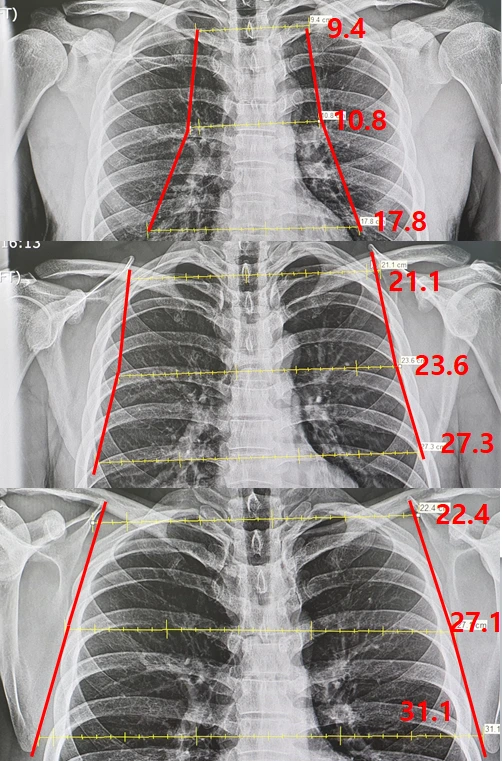

비교적 최근에 유튜브 Shorts 와 틱톡 에서 유행했던 어깨의 중요성 이라는 영상을 보신 분들이 있겠죠? 그에 착안하여 신쌤이 1. 견갑골을 완전히 후인하강 했을때, 2. 일상상태에서 힘을 빼고, 3. 견갑골을 뺀 "라인업" 상태 에서 X-ray 를 촬영하여 견갑골 사이의 거리를 측정해 보기로 했습니다.

견갑측정방법.PNG 흉부 X-ray 기준으로 견갑골 사이의 거리를 위,중간,아래 지점으로 나누어 측정하여 비교하였다.

측정 기준은 견갑골의 맨 위와 아래사이의 너비, 그리고 중간지점의 너비를 측정했는데, 견갑골의 특성상 위쪽을 축으로 아래부분이 바깥으로 회전하는 움직임을 그리기 때문에 한 곳만 측정하는 것 보단 이렇게 나눠서 측정하는 편이 더 좋은 결과를 얻을것이라고 생각했습니다.

x-ray.PNG 맨 위부터 1. 견갑골 후인하강 / 2. 일상상태에서 힘빼고 / 3. 광배를 뺀 "라인업" 포지션

견갑골을 후인하강 했을때는 평소상태와 비교했을때 상부부터 하부로 55.4%, 54.2%, 34.8% 견갑골 사이 너비가 감소(절반 이하로 감소)

했으며 반대로

견갑골을 밖으로 빼는 라인업 포지션을 했을 때는 6.2%, 14.8%, 14% 늘어나는 결과

를 보였습니다.

단순 수치를 보았을 때 키 174cm의 남자 헬스 중급자(신쌤 개인 의견) 기준으로 견갑을 완전히 후인하강 하면 견갑의 너비가 약 10cm정도 줄어들며, 반대로 견갑을 밖으로 빼면 평소상태보다 4cm정도 넓어 보이는 효과가 있다고 볼 수 있겠습니다. 물론 신쌤은 견갑을 빼는 포지션을 많이 연습하지 않으므로 이에 익숙한 사람이라면 더 넓은 기대값을 가질 수도 있겠다는 생각은 덤입니다.

재형 vs 원익.PNG 좌측이 웨이트 트레이닝한 신쌤의 후인하강과 평소상태, 우측이 의사1의 후인하강과 평소상태

상당히 흥미로운 결과가 나왔는데,

후인하강 한 상태에서는 오히려 운동을 하지 않은 의사1이 견갑골 사이의 거리가 미세하지만 더 넓게(0.5 - 1.3cm) 나왔지만,

평소 상태에서는 신쌤이 의사1에 비해 4-6.4cm 정도 더 넓게 측정

되었음을 확인할 수 있습니다.